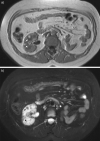

Figure 8.

Abdominal magnetic resonance imaging of a patient with tuberous sclerosis complex lymphangioleiomyomatosis and multiple small renal angiomyolipomas (arrows) in T1-weighted images (a) and fat suppression signal sequences (b). Left nephrectomy was performed for a large angiomyolipoma.